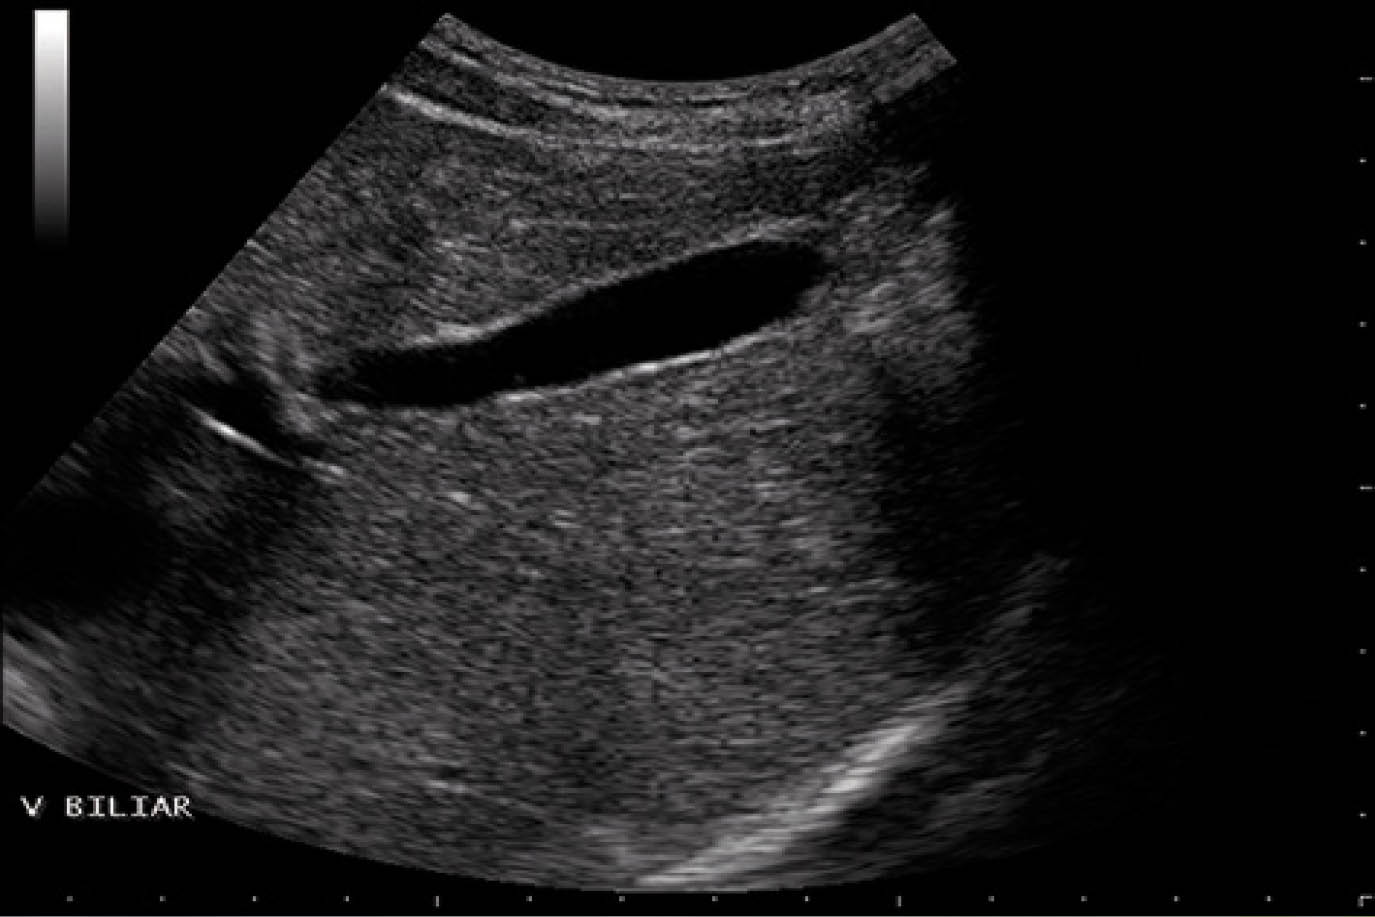

En la imagenología la exploración por US el cálculo se visualiza como una estructura muy ecogénica; rodeada de líquido con una sombra acústica posterior. En la colecistitis aguda alitiásica el diagnóstico ecográfico se dificulta, ya que solo en un 60 % de los casos se puede observar engrosamiento de la pared mayor a 3 mm . Otros datos importantes son presencia de lodo biliar con ecos de baja longitud y tiene la particularidad de no producir sombra acústica posterior.

En la dilatación de la vía biliar podemos observar que el colédoco puede tener una medida mayor de 6 mm por lo que podemos apreciar estructuras tubulares de baja ecogenicidad paralelas a las ramificaciones de la vena porta.